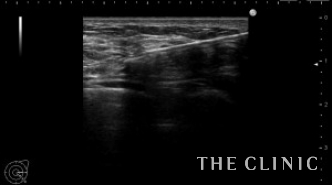

左乳腺下にオイルシストが2個ありました。

エコー下に穿刺吸引しました。

白濁したオイルが引けました。この後、コンデンスリッチ豊胸を行いました。